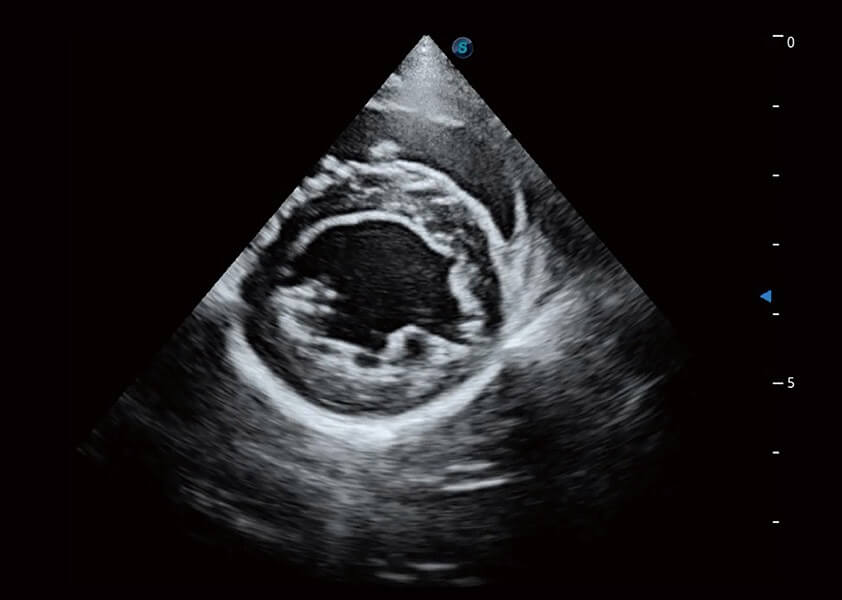

ProPet 60 作為一款高端臺式動物超聲設(shè)備,為動物醫(yī)生的日常診斷提供了一系列貼合動物臨床需求、解決臨床實(shí)際問題的高級成像功能。憑借全系列高清探頭,滿足醫(yī)生對腹部、心臟、生殖、淺表、肌骨等成像的所有需求,切實(shí)幫助您提升檢查效率,提高診斷信心。